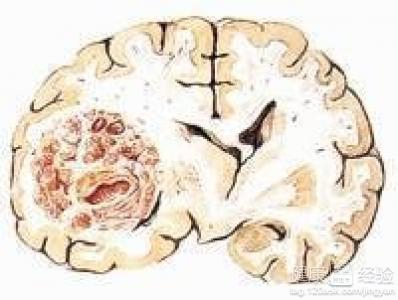

新生兒顱內囊腫怎麼治療

從孩子剛開始出生時候我們都沒有發現孩子有什麼異常的現象,全家都沉浸在有孩子的喜悅中,都沒有意識到危害慢慢的離我們很近,是在最近的時候,我發現孩子突然就開始出現了一種惡心的現象,給孩子吃東西的時候孩子都不會吃,並且我還發現孩子的出生到現在都比較奢睡,而及時給孩子檢查了一遍過後,醫生說孩子患上了顱內囊腫,我現在很想知道新生兒顱內囊腫怎麼治療?

1如果孩子出生的時候都患上了這種顱內囊腫疾病的話,那麼要考慮孩子的疾病是屬於先天性的疾病,如果是先天性的疾病話,則做治療的時候就必須要及時,不然對孩子來說傷害很大。

2治療這種顱內囊腫疾病的時候需要根據孩子的症狀來決定,如果無占位效應或政治的蛛網膜囊腫,那麼就可以不給孩子治療,如果一旦還有症狀,並且嚴重,那麼就需要給孩子采用手術來做治療。

3手術治療方法有很多種,可以給孩子采用周圍腦池溝通術來做治療,同時也可以選擇開顱手術切除部分囊壁的方法來治療,但是做治療的時候需要配合醫生來給孩子治療,如果嚴重,治療就必須要及時。

家長們對孩子這種疾病做治療的時候千萬不要著急,如果孩子沒有症狀,那麼是會自行康復的,期間要讓孩子快樂的成長,給孩子更多關愛,讓孩子的房間多通風。